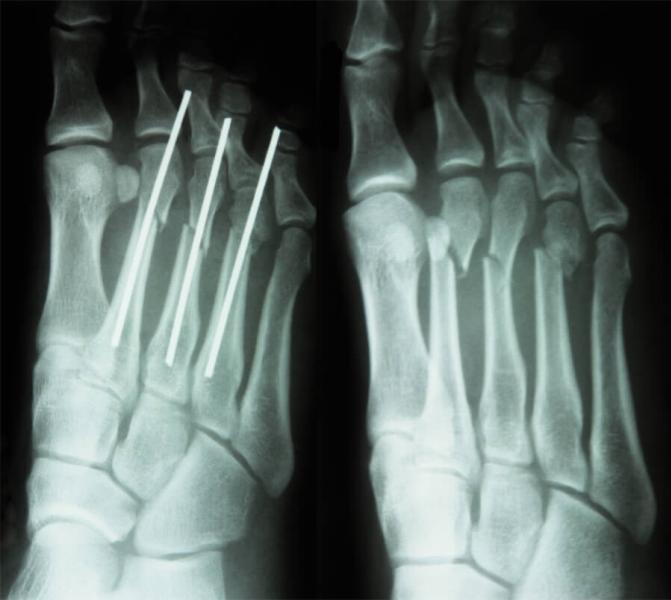

Перелом 2, 3, 4 плюсневых костей левой стопы

Гипс 23.01.2024 г.